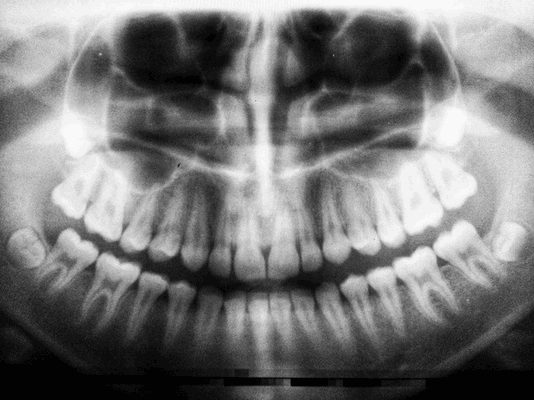

Чтобы оценить состояние зубов и увидеть скрытые дефекты, обычно назначают ортопантомограмму (панорамный снимок) или КТ. Это не прихоть врача, а желание необходимость создать полноценную картину, с учетом всех деталей. К тому же, снимок может выявить воспалительные процессы, которые при осмотре незаметны.

Диагностическая подготовка

Проводится с целью выявить состояние костной ткани и зубных корней, исключить противопоказания. Если вы лечите один зуб, будет достаточно прицельного снимка (рентген). Если врачу необходимо увидеть картину целиком, нужен обзорный снимок (ортопантомограмма). Перед имплантацией вас направят на компьютерную томографию.

Панорамный снимок, КТ. Позволяют увидеть состояние челюстной системы, костной ткани, нервов, носовых пазух. На основании этого врач расписывает план лечения.